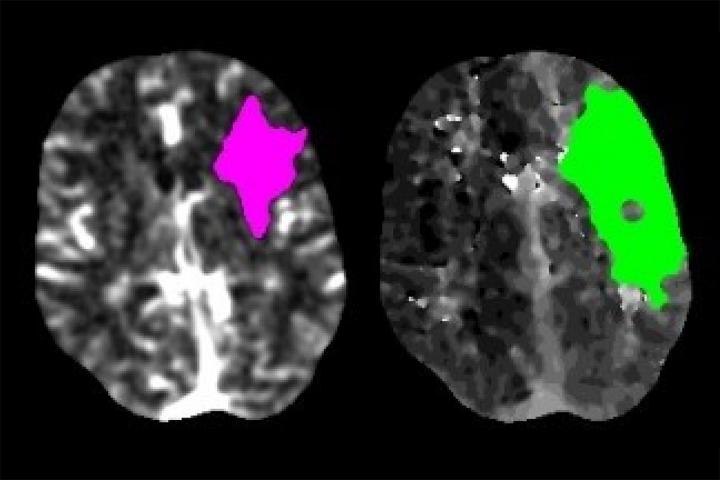

image: Scans of a stroke patient's brain show the area where tissue has died (magenta) and where tissue is damaged but may still be saved with prompt intervention (green). A study from Washington University School of Medicine in St. Louis has found that stroke evaluations fell by nearly 40% during a period of the COVID-19 pandemic, suggesting that many stroke patients are not seeking potentially life-saving medical treatment.

When patients arrive at a hospital and are showing signs of a stroke, they often get a brain scan so doctors can identify what kind of stroke has occurred and choose the most effective treatment. Many hospitals, including Barnes-Jewish Hospital, use software known as RAPID to analyze such brain scans. Kansagra and colleagues assessed how often the software was used in February, before the pandemic, and during a two-week period from March 26 to April 8, when much of the country was under shelter-in-place orders.